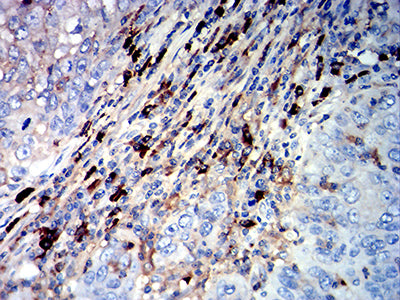

| IHC | 1/200-1/1000 |

Product Image |